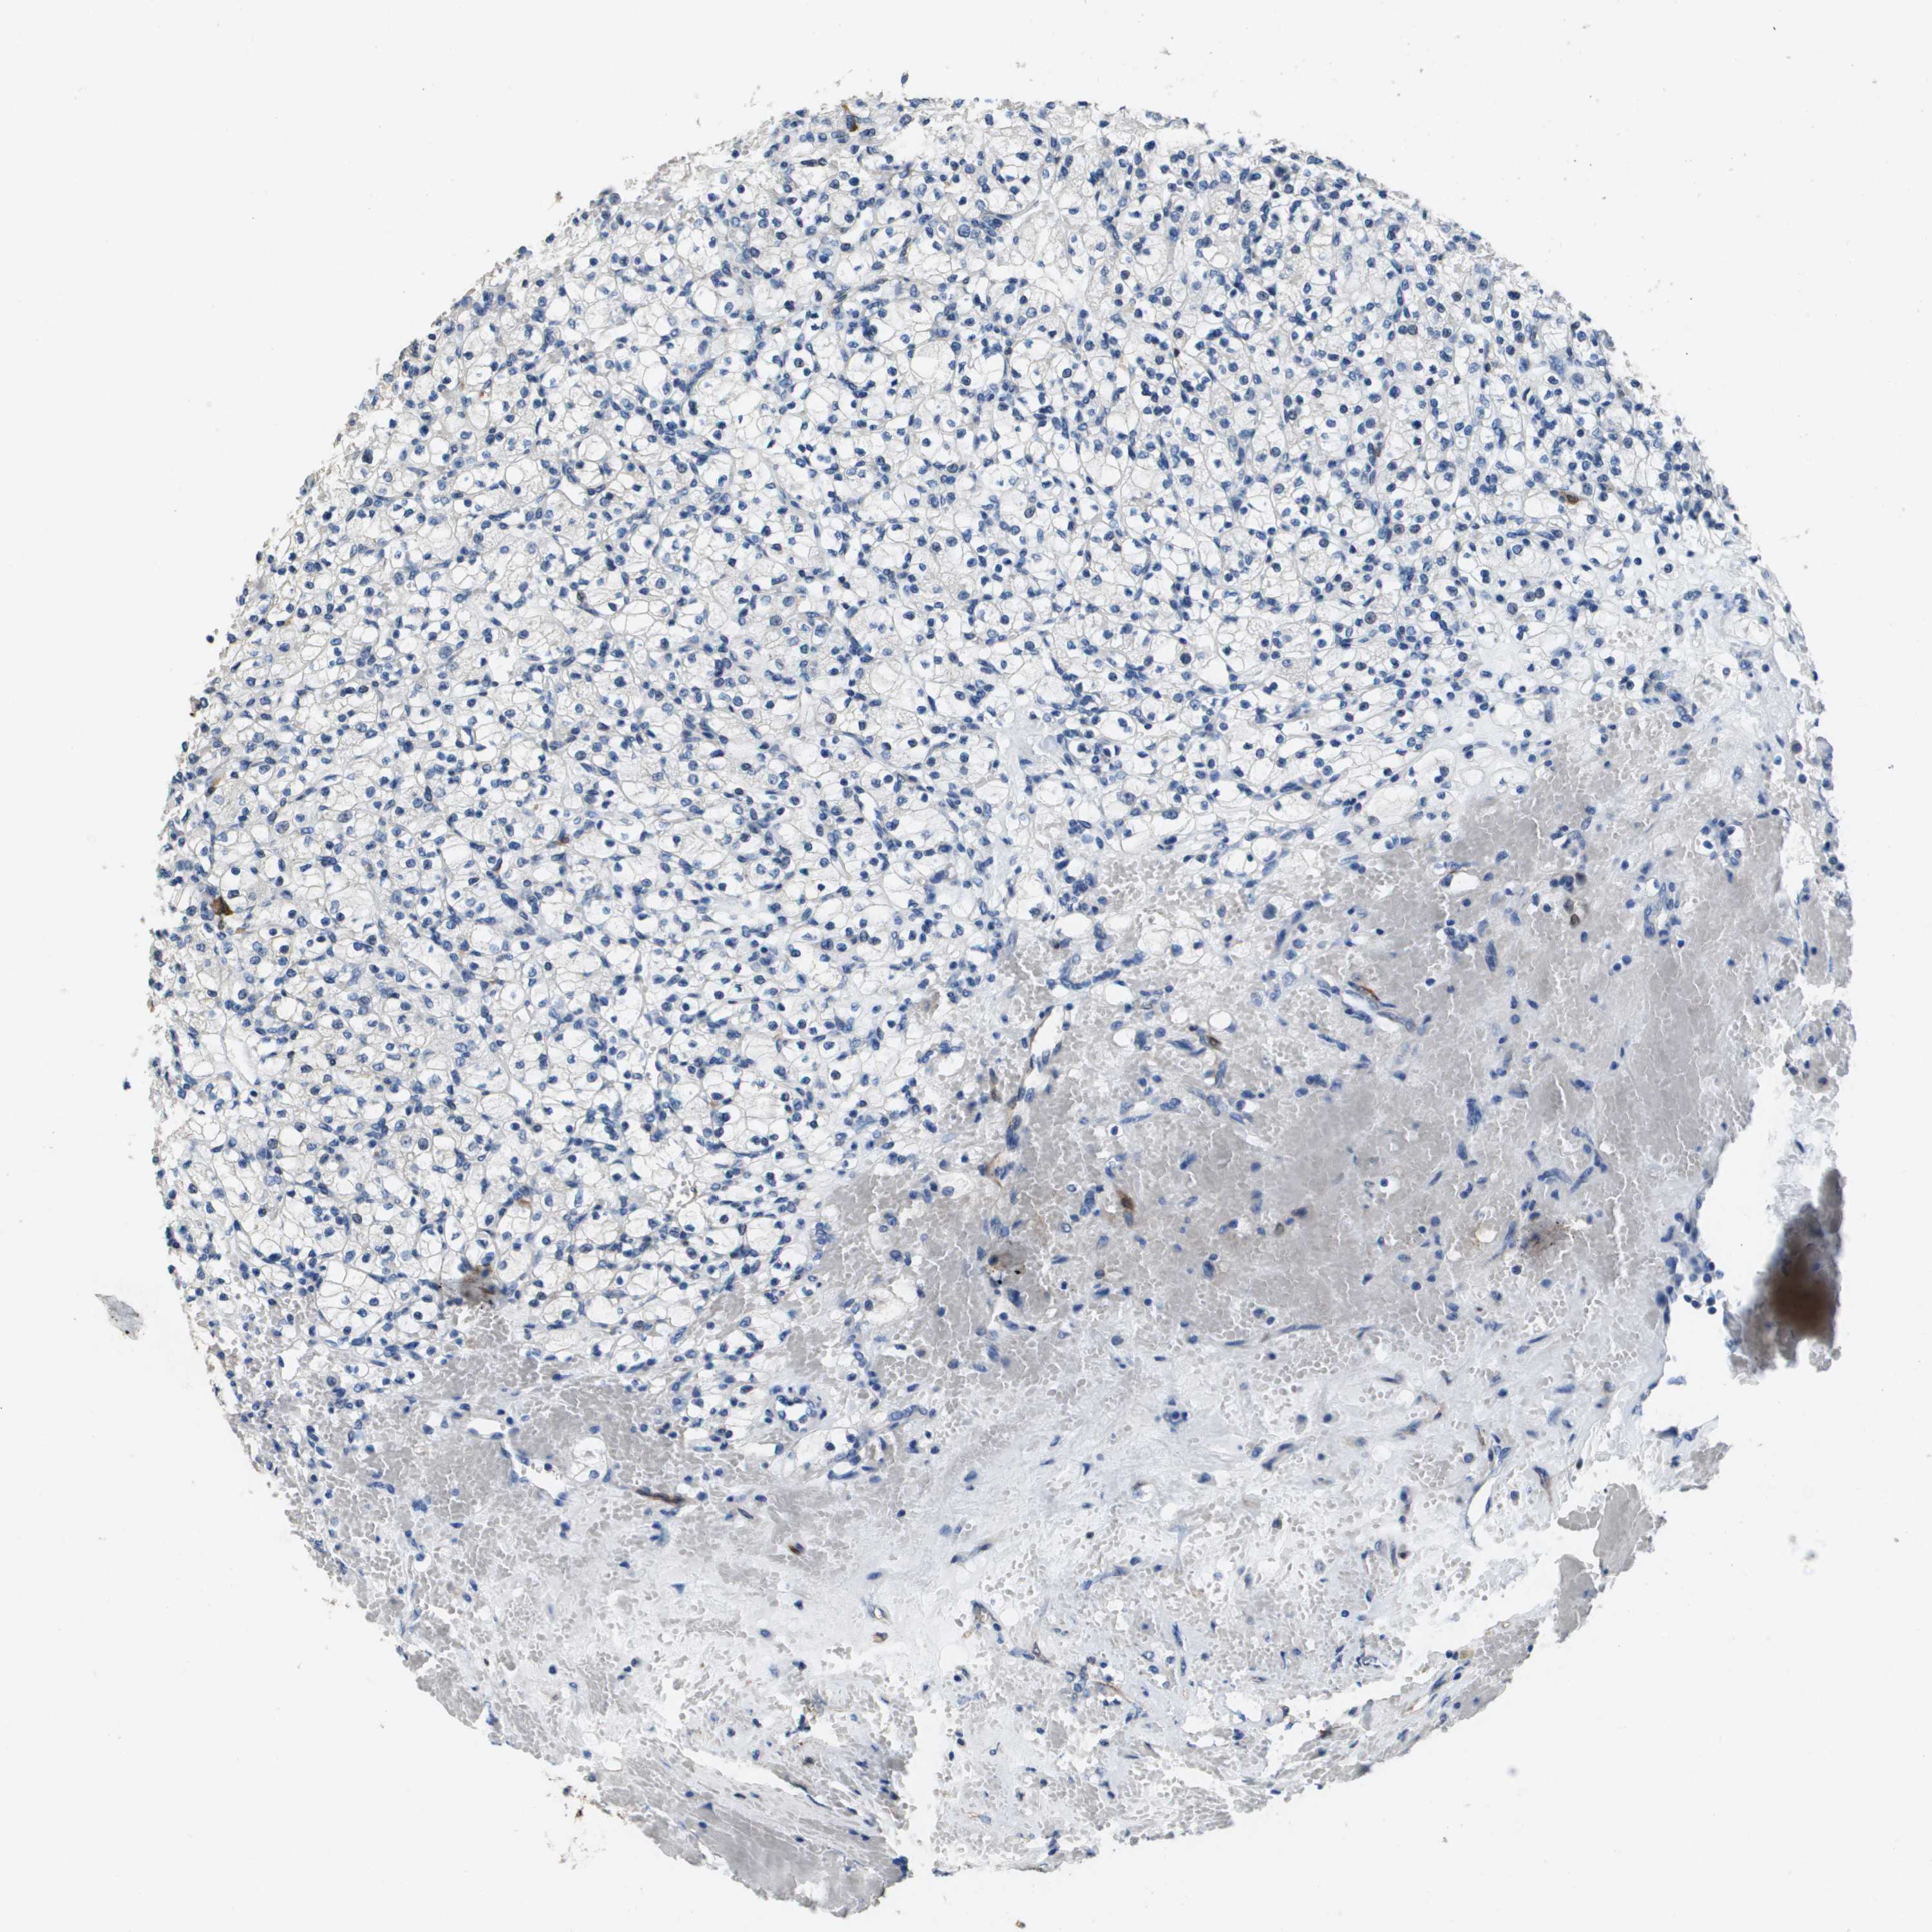

Renal cancer

Kidney chromophobe

KIDNEY CHROMOPHOBE (TCGA) - Interactive survival scatter ploti

The Survival Scatter plot shows the clinical status (i.e. dead or alive) for all individuals in the patient cohort, based on the same data that underlies the corresponding Kaplan-Meier plots. Patients that are alive at last time for follow-up are shown in blue and patients who have died during the study are shown in red.

The x-axis shows the expression levels (FPKM) of the investigated gene in the tumor tissue at the time of diagnosis. The y-axis shows the follow-up time after diagnosis (years). Both axes are complimented with kernel density curves demonstrating the data density over the axes. The top density plot shows the expression levels (FPKM) distribution among dead (red) and alive patients (blue). The right density plot shows the data density of the survived years of dead patients with high and low expression levels respectively, stratified using the cutoff indicated by the vertical dashed line through the Survival Scatter plot. This cutoff is automatically defined based on the FPKM cutoff that minimizes the p-score. The cutoff can be changed by dragging the vertical line or by entering a cutoff value in the square labeled "Current cut-off".

Under the Survival Scatter plot the p-score landscape (black curve; left axis) is shown together with dead median separation (red curve; right axis). Dead median separation is the difference in median mRNA expression between patients who have died with high and low expression, respectively. It is calculated as follows: median FPKM expression of dead patients with high expression - median FPKM expression of dead patients with low expression. This is intended to aid the user in visually exploring custom cutoffs and the associated p-scores and dead median separation.

Individual patient data is displayed and can be filtered by clicking on one or more of the category buttons on the top of the page. Categories describing expression level and patient information include: high, low, alive, dead, female, male and tumor stages. The scale of the x-axis can be toggled between linear and log-scale by clicking on the "x log" button. Mouse-over function shows TCGA ID, patient information and mRNA expression (FPKM) for each patient.

& Survival analysisi

Kaplan-Meier plots summarize results from analysis of correlation between mRNA expression level and patient survival. Patients were divided based on level of expression into one of the two groups "low" (under cut off) or "high" (over cut off). X-axis shows time for survival (years) and y-axis shows the probability of survival, where 1.0 corresponds to 100 percent.

FABP5 is not prognostic in Kidney Chromophobe (TCGA)